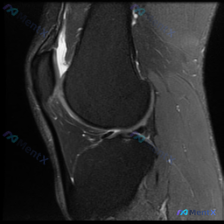

今天整理一份很有代表性的膝关节MRI读片病例,和大家分享一下思路。这个病例最初是被怀疑有半月板异常,我们一起来看看实际情况。 病例影像基本信息 这是一份膝关节MRI冠状位T2加权图像,我们先梳理所有基础观察: 1. 股骨远端、胫骨近端骨髓信号正常,没有明显骨髓水肿 2. 半月板情况:内侧半月板体部形...